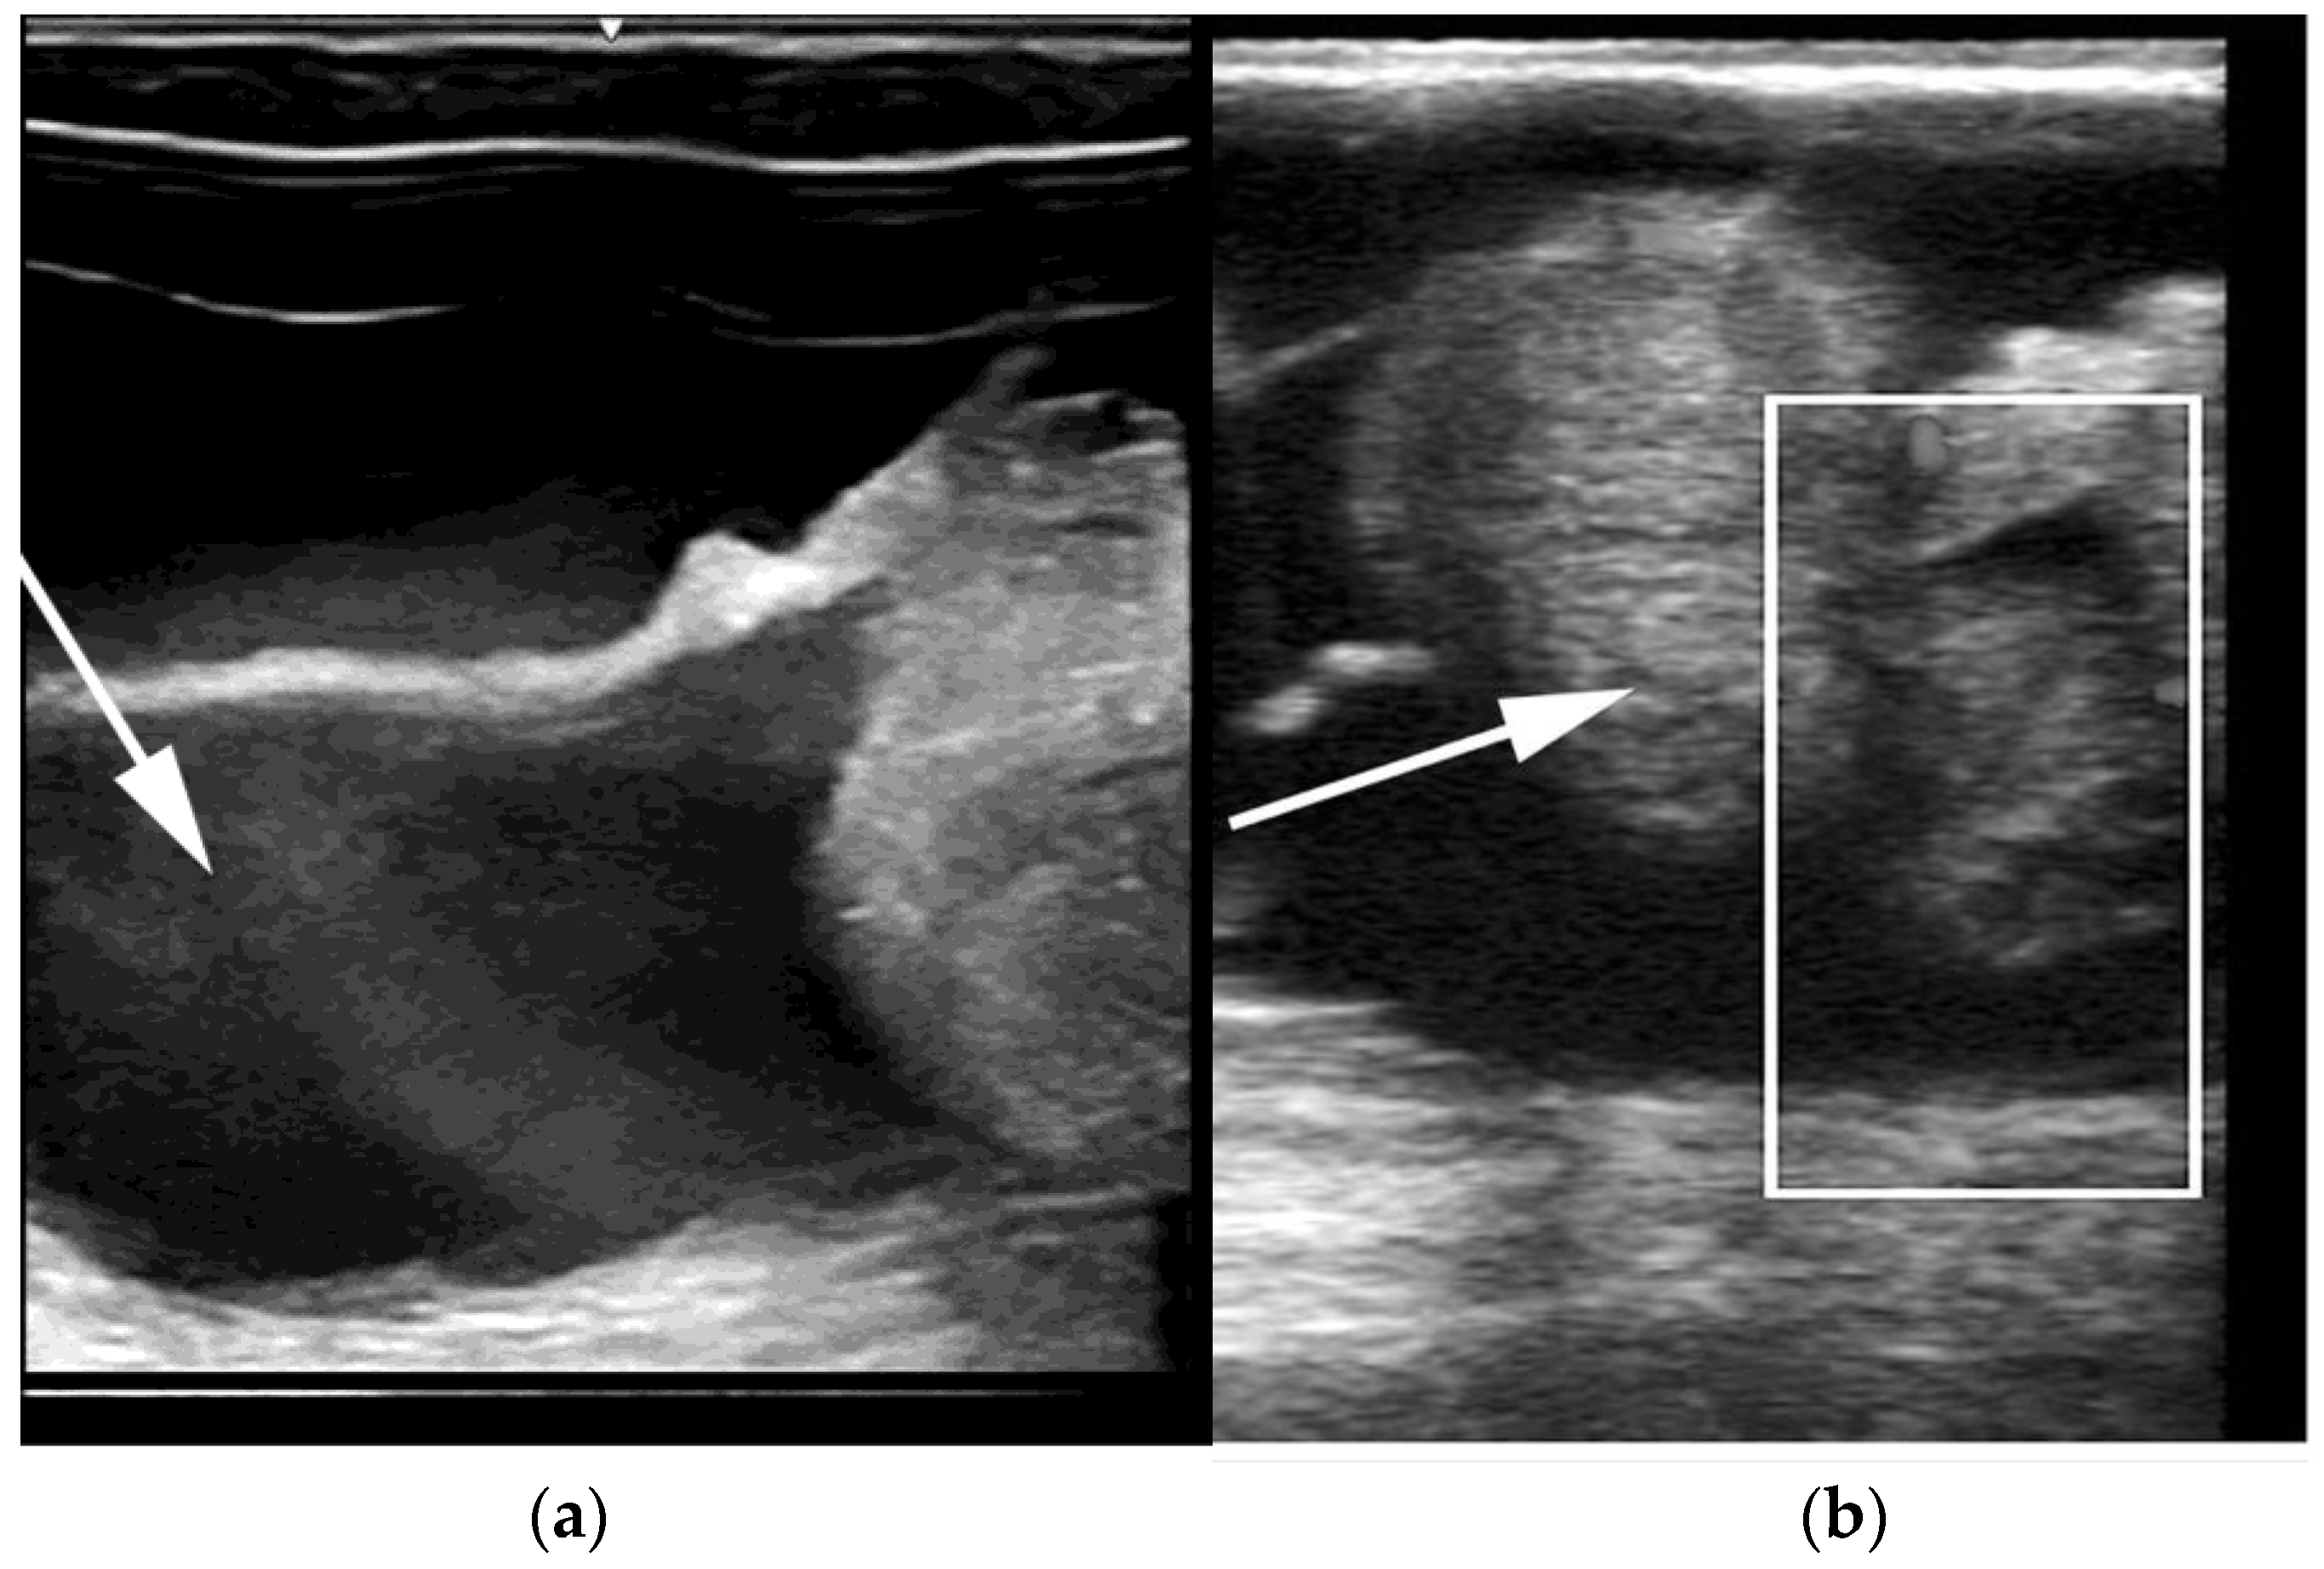

Hydrobursitis, or ovariobursitis, is a peculiar disorder in camels characterized by the accumulation of varying amounts of fluid within the ovarian bursa [44]. This pathology has been reported worldwide but appears to have a higher incidence in the Middle East [1,23,34,37,44,45]. The etiopathogenesis remains unclear. However, based on biochemical analysis of the fluid content, in some cases, the cause is attributed to recurrent ruptures of hemorrhagic follicles [44,46]. A variety of bacteria have been isolated (Actinobacillus spp., Escherichia coli, Klebsiella pneumoniae, Pseudomonas aeruginosa, Staphylococcus spp., and Streptococcus spp., as well as others) [46,47,48]. More recently, Chlamydophila abortus (Chlamydia abortus) infection has been demonstrated in several cases of hydrobursitis [49]. The role of Chlamydia spp., Brucella spp., and Campylobacter spp. in this pathology merits further investigation. Clinically, hydrobursitis is suspected when uterine retraction is not possible despite normal size of the uterus and cervix. Confirmation is easily obtained by transrectal or transcutaneous inguinal ultrasonography (Figure 6). Bilateral development is more frequent in females with long-standing infertility (more than 2 years) [44]. The main signs include repeat breeding, early embryo loss, and abortion [1,14,44,45]. Endometritis, uterine adhesions, and pyometra may also be diagnosed in cases of hydrobursitis [14,36,46]. Treatment with oxytetracycline (20 mg/kg IM for 7 days) combined with intrauterine infusion of metacresol sulfonic acid and formaldehyde solution was shown to be effective in restoring fertility if the lesion is small (<3 cm) [50]. Surgical excision of the affected side is the only treatment for large lesions (Figure 7) [44].

Figure 6. Ultrasonographic images of hydrobursitis in camels. (a) Arrow: echogenic fluid within the bursa; (b) Arrow: abnormal ovary contained in the fluid-filled bursa.